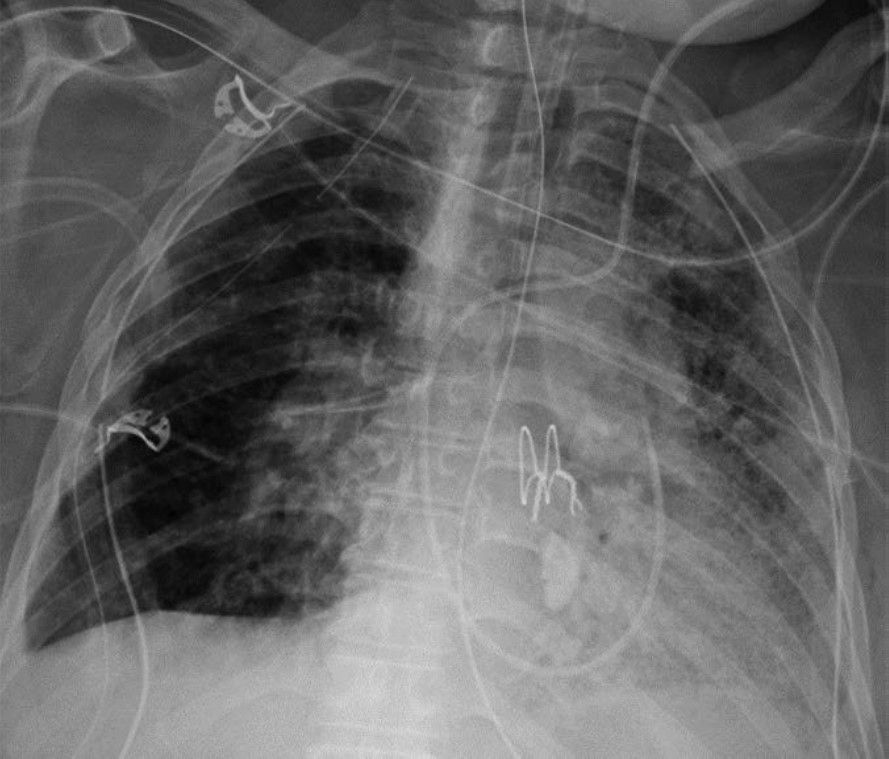

Lung herniation can occur anytime after lung transplant. A major risk factor for lung herniation is increased intrathoracic pressure, as can be seen in patients with persistent cough due to pneumonia or aspiration after transplant. On imaging, herniated lung has an abnormal contour with a portion of lung bulging into the chest wall; this can occur at surgical sites (such as thoracotomy incisions) or at intercostal spaces. Mild herniation involving a small portion of the lung allograft with normal-appearing parenchyma is not worrisome. However, herniation involving a large portion of the allograft or deep herniation into the chest wall places the patient at risk for atelectasis, ischemia, infarction, and gangrene of the herniated lung, all of which can manifest as opacities within the herniated portion of lung. Surgical repair of the chest wall may be necessary in cases of pulmonary infarction or gangrene. Figure 8 shows a patient with lung herniation.

Fig. 8—Patient with history of bilateral lung transplant who presented with lung herniation. Frontal chest radiograph shows mild herniation of small portion of right upper lung into chest wall at thoracotomy incision site (arrow).